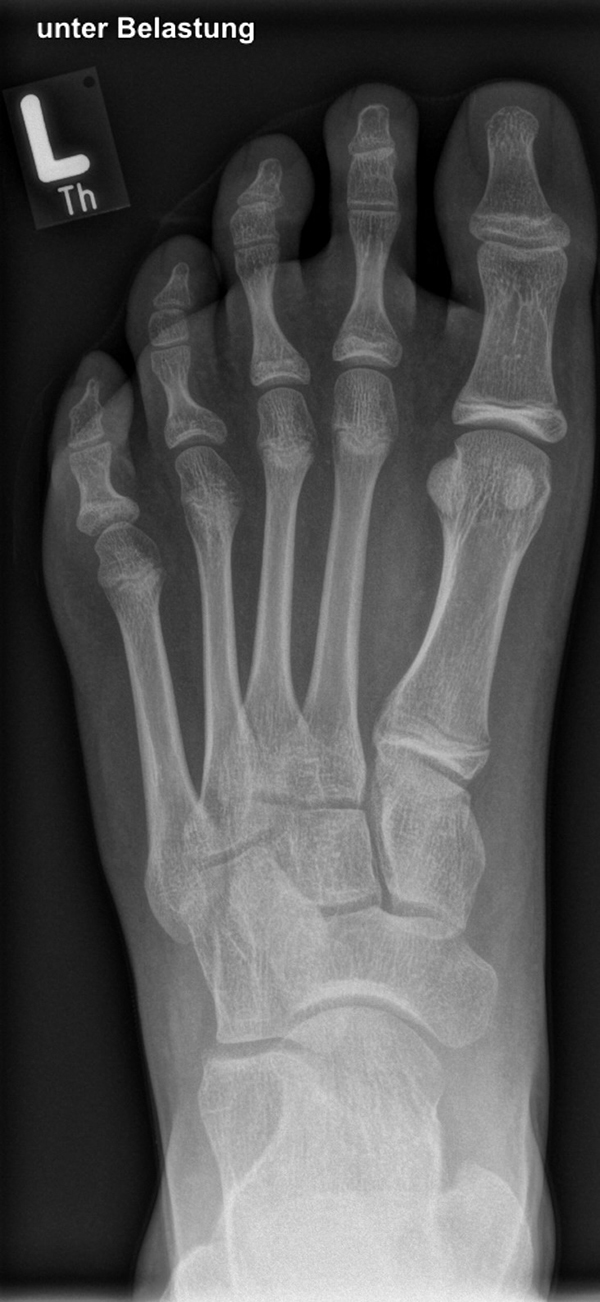

Diagnostisches Vorgehen

Damit die minimalinvasive Fußchirurgie zur Korrektur kindlicher oder jugendlicher Fußdeformitäten erfolgreich angewendet werden kann, erfordert die präoperative Diagnostik Röntgenbilder in drei Ebenen am stehenden Fuß. Röntgenbilder ohne Belastung des Fußes sind nicht zielführend. Im Fall von schweren Rückfußdeformitäten wird das obere Sprunggelenk in die radiologische Diagnostik mit einbezogen in Kombination mit der Rückfußaufnahme unter Belastung („Saltzman View“). Das OSG wird in zwei Ebenen geröntgt. Die streng seitliche Aufnahme des OSG kann bei den komplexen Fußdeformitäten mit der seitlichen Aufnahme des Fußes unter Belastung kombiniert werden. Das reduziert die diagnostische Strahlenbelastung der Kinder.

Indikationen für die beschriebenen Röntgenaufnahmen sind Klumpfußdeformitäten zur Beurteilung eines „flat top talus“ oder neurologische Grunderkrankungen mit varischer Fersenstellung wie zum Beispiel bei HSMN (Hereditäre Sensorische Motorische Neuropathie).